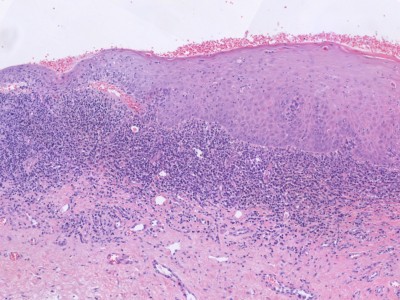

PA:

Dunne, vlakke epidermis, vaak

zijn de bovenste lagen (stratum corneum, stratum spinosum) afwezig, soms ontbreekt

de hele epidermis t.g.v. subepidermale splijting. Keratinocyten zijn vaak afgeplat

(diamant of rozenblaadjes vorm) en gescheiden door intracellulair oedeem. In

de epidermis zijn soms erytrocyten aanwezig, soms is er keratinocyt necrose.

In de oppervlakkige dermis (stratum papillare) bestaat een bandvormig infiltraat

bestaande uit extreem veel plasmacellen. Ook varianten met minder plasmacellen

komen voor. Voorts gedilateerde capillairen, en soms erytrocytenextravasatie

en hemosiderine pigment.

ingescande coupe (zoom) |

hoge resolutie PA-foto: Kevin Kwee en Afdeling Pathologie MUMC. Klik

op de afbeelding om in te zoomen.